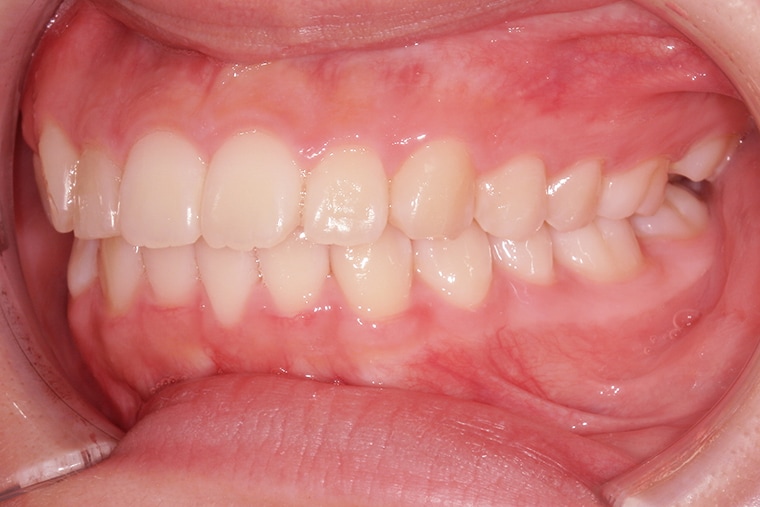

Case Study15歳女性出っ歯のマウスピース矯正-矯正期間10ヶ月

AFTER

約10ヶ月の矯正期間を経て、上の前歯の出っ歯は改善され、口を閉じることが自然にできるようになりました。歯並びが整ったことで笑顔に自信が持てるようになり、日常生活でも以前より表情が明るくなったのを感じます。学校生活や友達との会話でも、口元を気にすることが少なくなり、本人も嬉しそうです。

矯正を始める前は不安もありましたが、結果的に歯並びがキレイになり、健康面でも噛み合わせが改善されたことで安心しています。母としても、この変化を間近で見られたことは本当に嬉しく、伊藤歯科さんで矯正を決めて良かったと感じています。